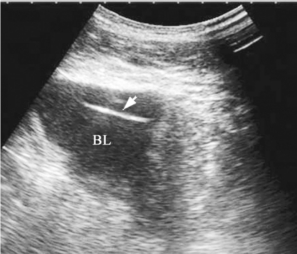

图30-6 膀胱异物声像图

箭头所指条状强回声为膀胱内异物